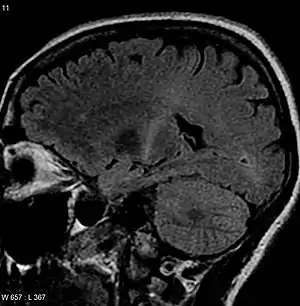

The defining feature of ALS is the death of both upper motor neurons (located in the motor cortex of the brain) and lower motor neurons (located in the brainstem and spinal cord).[79] In ALS with frontotemporal dementia, neurons throughout the frontal and temporal lobes of the brain die as well.[35] The pathological hallmark of ALS is the presence of inclusion bodies (abnormal aggregations of protein) in the cytoplasm of motor neurons. In about 97% of people with ALS, the main component of the inclusion bodies is TDP-43 protein;[10] however, in those with SOD1 or FUS mutations, the main component is SOD1 protein or FUS protein, respectively.[27] The gross pathology of ALS, which are features of the disease that can be seen with the naked eye, include skeletal muscle atrophy, motor cortex atrophy, sclerosis of the corticospinal and corticobulbar tracts, thinning of the hypoglossal nerves (which control the tongue), and thinning of the anterior roots of the spinal cord.[10] Aside from the death of motor neurons, two other characteristics common to most ALS variants are focal initial pathology, meaning that symptoms start in a single spinal cord region, and progressive continuous spread, meaning that symptoms spread to additional regions over time. Prion-like propagation of misfolded proteins from cell to cell may explain why ALS starts in one area and spreads to others.[27]